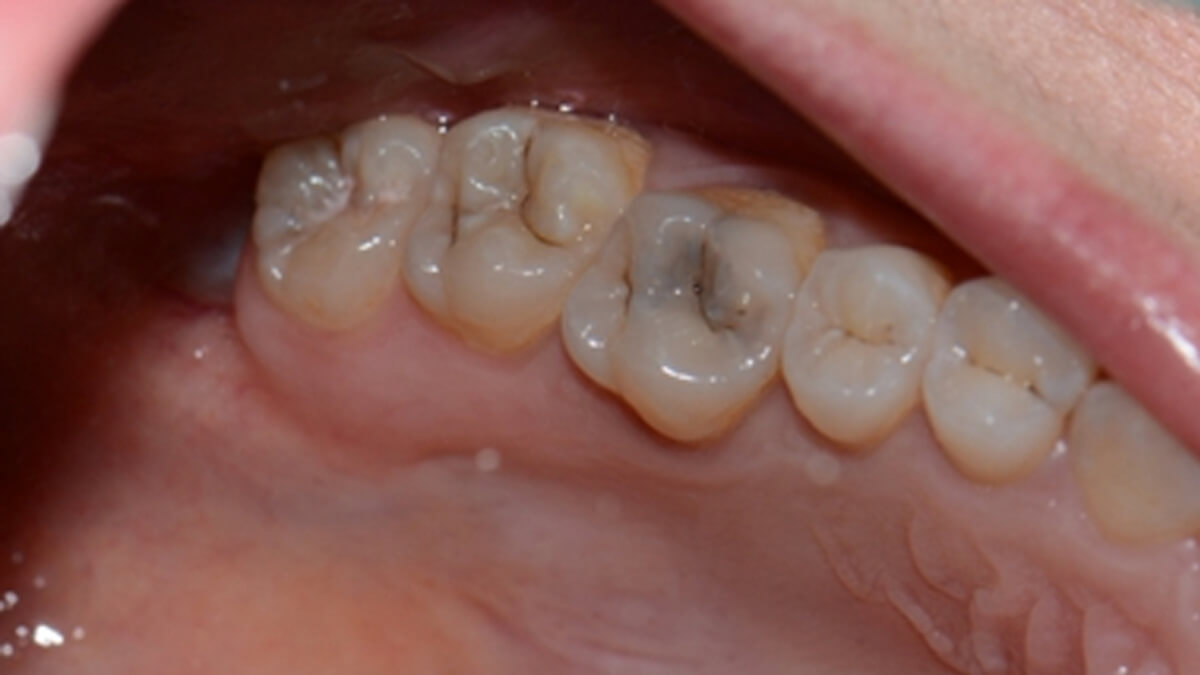

Általában ha a fognak csak egy kisebb része szuvas, a hiányzó rész kitisztítás után tömőanyaggal pótolható. A töméskészítést helyi érzéstelenítésben végezzük, egy alkalmat vesz igénybe. A tömőanyag egy speciális műanyag, kompozit, amely mind színében, mind fizikai tulajdonságaiban nagymértékben hasonlít a természetes foghoz, ezért alkalmas tartós és esztétikus tömések készítésére. Töméskészítés során a gyurmaszerű anyagot kis adagokban helyezzük az üregbe, majd az egyes rétegeket speciális lámpával világítjuk meg, melynek hatására megszilárdulnak. A tömés elkészültével az anyag kötése befejeződik, a fog terhelhető.

A tömőanyag tulajdonságaiból adódóan ma már, ha az üreg nem túl nagy, minden fogcsoport tömésére alkalmazható. Rágófogakban képes helyreállítani a funkciót, azaz egy erős, a rágóerőkkel szemben ellenálló tömés készíthető, frontfogakba (metszőfogak) pedig készülhet olyan esztétikus, észrevehetetlen tömés, mely kedvezően befolyásolhatja megjelenésünket, arckarakterünket.